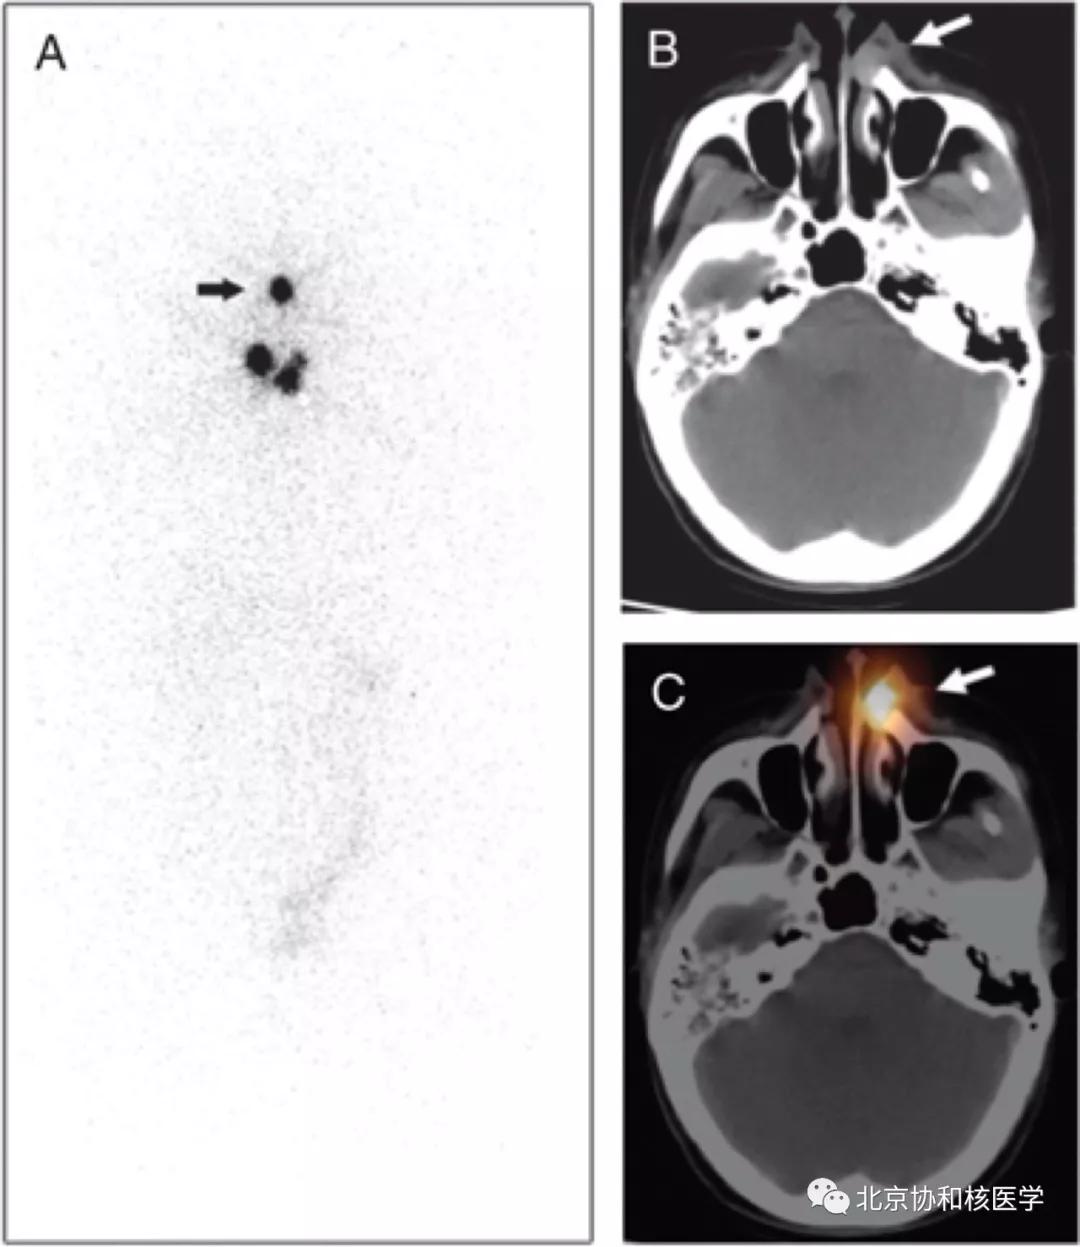

鼻腔脓肿所致碘摄取,其下方可见颈部残余甲状腺:

鼻腔息肉所致碘摄取,同时可见颈部残余甲状腺组织: